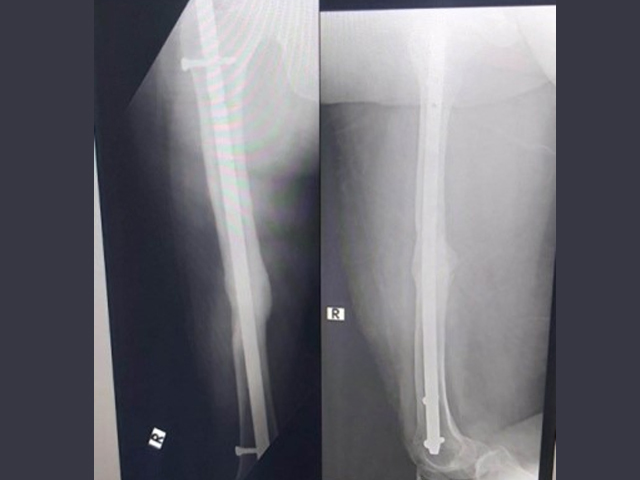

Trauma and Emergency Care:

The department operates a dedicated Level-I trauma center to manage accidents and emergencies. This facility provides prompt and effective treatment for patients with polytrauma, fractures, dislocations, and other musculoskeletal injuries. The trauma center is supported by an efficient Intensive Care Unit (ICU), anaesthetists, and Trauma Surgeons We also serve as a referral center for managing complications following trauma, such as infections, non-unions, and deformities.

Treatment of all routine, complex trauma and neglected trauma

1 JAMP EFFECTIVESS OF MINI HACKSAW BLADE ON HANDLE FOR REMOVING BENT INTRAMEDULLARY NAILS: A CASE SERIES

2 JAMP ASSEMENT OF FUNCTIONAL AND RADIOLOGICAL OUTCOME OF INFECTED